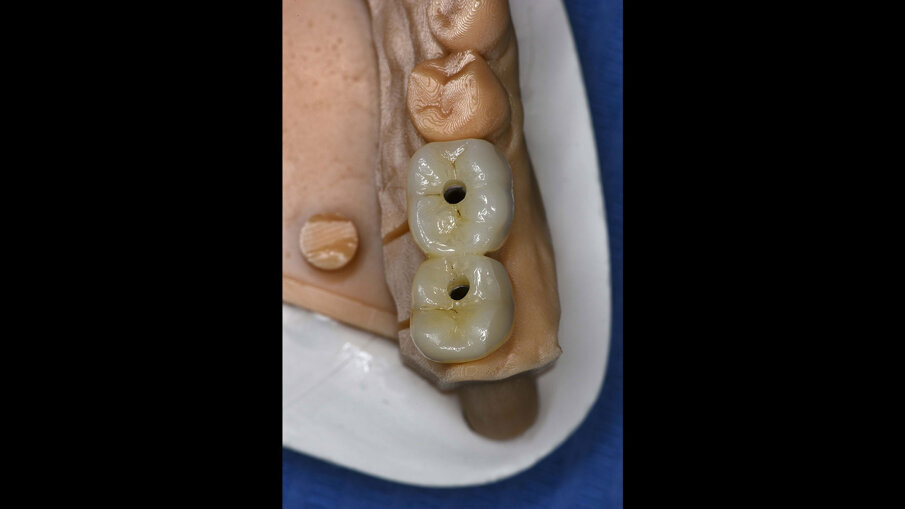

Dopo due settimane, è stata eseguita una scansione 3D con scan body e sono state consegnate due corone provvisorie avvitate sugli impianti, in modo da poter condizionare i tessuti molli peri-implantari (Figg. 11-12b). A causa di un’inadeguata banda di mucosa cheratinizzata sul versante vestibolare, è stato eseguito un intervento di vestiboloplastica con affondamento di fornice e innesto epitelio-connettivale prelevato dal palato (Figg. 13, 14). Dopo un’ulteriore maturazione dei tessuti, una nuova scansione ha permesso di dare informazioni all’odontotecnico circa il tragitto transmucoso ottenuto con i provvisori e sono state consegnate due corone definitive avvitate in zirconio (odt. Alessandro Giacometti; Figg. 15-19b). La paziente è stata seguita con controlli periodici clinici e radiografici a 6 mesi, 1 anno e 2 anni dal carico protesico (Figg. 20a, 20b).

Figg. 18a, 18b_Elementi definitivi in zirconio avvitati.